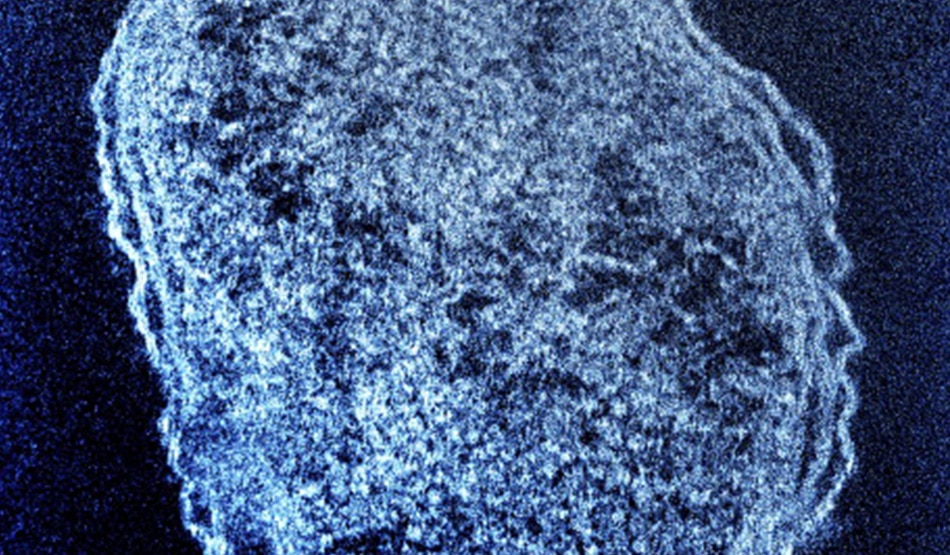

रिपोर्ट के अनुसार, आगरा के डिविजनल कमिश्नर अमित गुप्ता ने बताया कि इस बुखार के कारण कुछ लोगों की मौत भी हो चुकी है. इन मौतों के लिए स्क्रब टाइफस को जिम्मेदार ठहराया जा रहा है. ये डेंगू की तरह एक वेक्टर बॉर्न बीमारी है. स्क्रब टाइफस किसी वायरस के कारण नहीं बल्कि बैक्टीरिया के कारण होता है.

एक्सपर्ट्स और डॉक्टर्स के अनुसार, स्क्रब टाइफ्स ( Scrub Typhus) को शर्ब टाइफ्स भी कहते हैं. ये ओरिएंटिया त्सुत्सुगामुशी (Orientia Tsutsugamushi) नामक बैक्टीरिया से होता है. इसे बुश टाइफस के नाम से भी जाना जाता है. ये संक्रमित चिगर्स (लार्वा माइट्स) के काटने से लोगों में फैलता है.